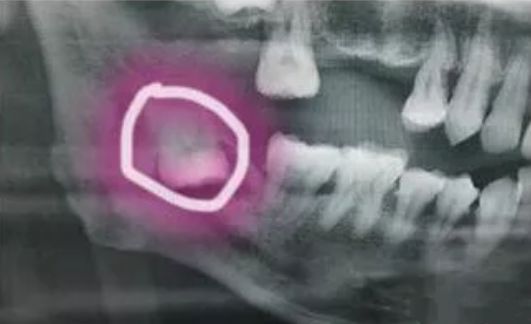

后来,身心俱疲的杨先生到某市口腔医院检查,检查结果令杨先生愕然,X牙片显示,杨先生的智齿竟掉到了左侧下颌骨内侧的深部间隙里。

牙医表示,由于患者的智齿位置深,朝舌向倒置生长,紧贴下牙槽神经管,舌侧骨壁薄弱,所以之前拔牙时医生可能没注意到。而且这颗智齿的位置,一直伴随着颌骨的运动而改变。

最后介绍一下,牙根弯曲,骑在下颌管上的智齿...

由于下颌管内神经丰富,拔除的时候需要极度小心,而且看长相也知道这种模式的拔牙,非常难拔,也非常贵!